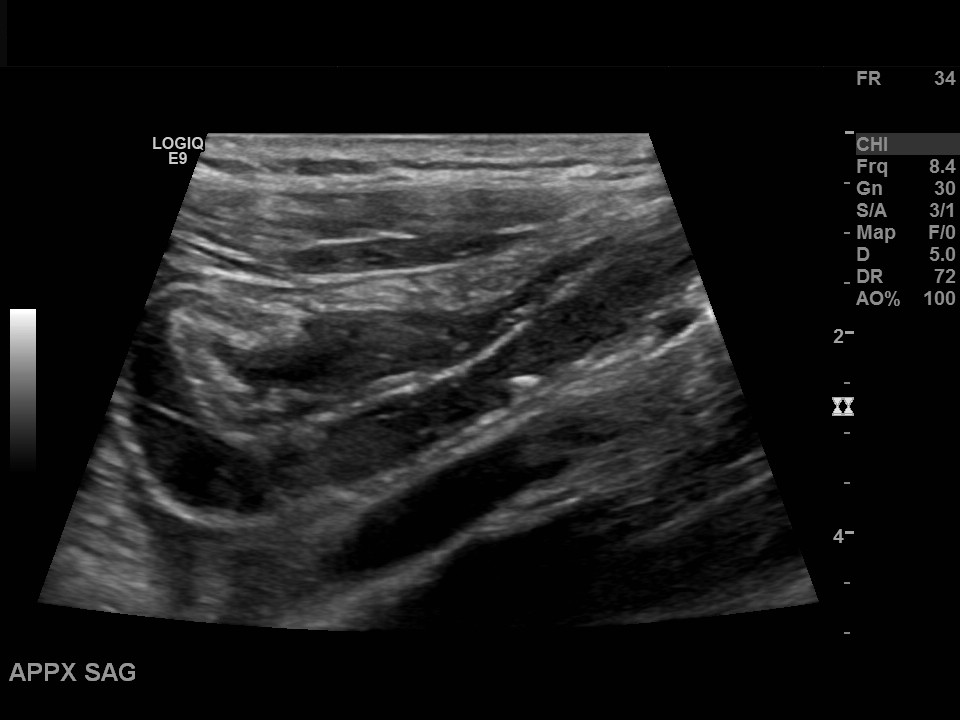

Appendicitis 13

Acute appendicitis @ 1 cm with L2-9mhz and L6-24mhz transducer GE Logiq e10.